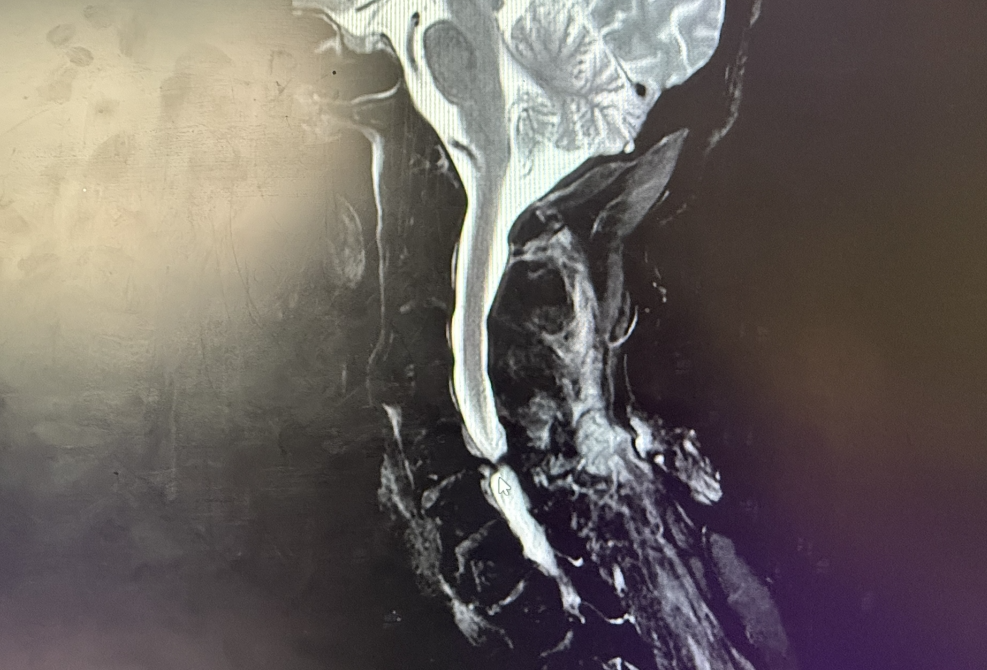

时间就是脊髓功能恢复的关键!我院立即启动急救绿色通道。上午9点22分,患者完成颈椎MRI检查,结果触目惊心:C5-6水平椎管严重狭窄,脊髓明显受压!脊髓内出现异常信号灶(高度提示急性损伤或变性)!同时存在C3-6椎间盘突出、颈椎退变、黄韧带肥厚等问题。

(术前检查)

骨科专家团队迅速会诊,结合病史和影像学检查,明确诊断为:急性颈脊髓损伤(ASIA分级待定,但双下肢瘫痪、感觉消失提示损伤严重)颈椎骨折(Chance型)、双下肢瘫痪。